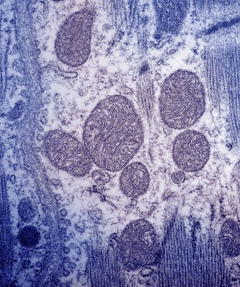

Методы цитологического исследования основаны на изучении под микроскопом строения клеток, клеточного состава жидкостей и тканей.

электронная микроскопия;